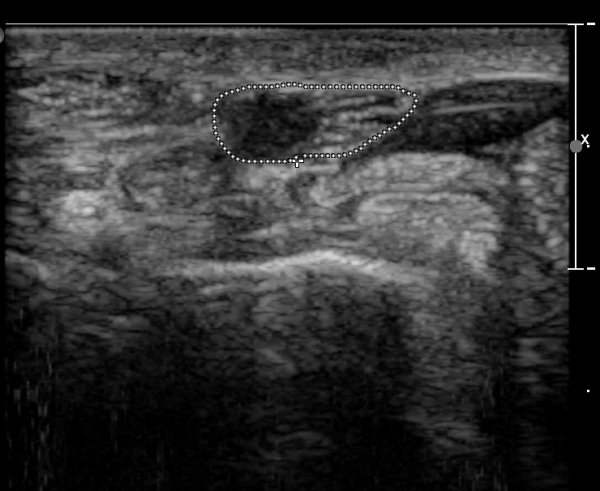

Å½ÃËÀÚ¸¦ ¸»´ÜÀ¸·Î À̵¿ÇÏÀÚ  Á¤Áß½Å굥 ¿äÃø ÀϺΰ¡ Àú¿¡ÄÚ Á¾±«·Î °üÂûµÊ(»çÁø 2).

Á¤Á߽Űæ Á¾´Ü¸é°Ë»ç¿¡¼­µµ ¼Õ¸ñ ¸»´ÜºÎ¿¡¼­ ¼ö±Ù°ü ±ÙÀ§ºÎ±îÁö À̾îÁø Àú¿¡ÄÚ

Á¾¾çÀÌ °üÂûµÊ(»çÁø 8, 9, 10, 11).

Á¾¾ç¿¡ ÀÇÇÑ Á¤Á߽Ű渻´Ü°¡ÁöÀÇ ¾Ð¹ÚÀÌ ÃßÁ¤µÇ¾úÀ¸³ª  ÃÊÀ½ÆÄ°Ë»ç»ó ¼Õ¸ñºÎÀ§¿¡¼­ Á¤Á߽Ű泻

Àú¿¡ÄÚ Á¾¾çÀÌ °üÂûµÇ°í Àú¿¡ÄÚ Á¾¾çÀÇ ½Å°æ³» À§Ä¡°¡ Âü°í¹®Çå¿¡¼­ º¸°íÇÑ ¹Ù¿Í °°ÀÌ

Á¤Á߽Ű泻¿¡¼­ µÎµ¢±ÙÀ°À» Áö¹èÇÏ´Â ¿îµ¿½Å°æÀÇ À§Ä¡¿Í ÀÏÄ¡ÇÏ¿© Á¤Á߽ŰæÁß¿¡¼­ µÎµ¢±ÙÀ°À»

Áö¹èÇÏ´Â ½Å°æ µ¢¾î¸®(fascicle)ÀÇ ½Å°æÁ¾À¸·Î ÃßÁ¤ÀÌ °¡´ÉÇϸç ÀÓ»óÀû ¼Ò°ß°úµµ ÀÏÄ¡ÇÑ´Ù.